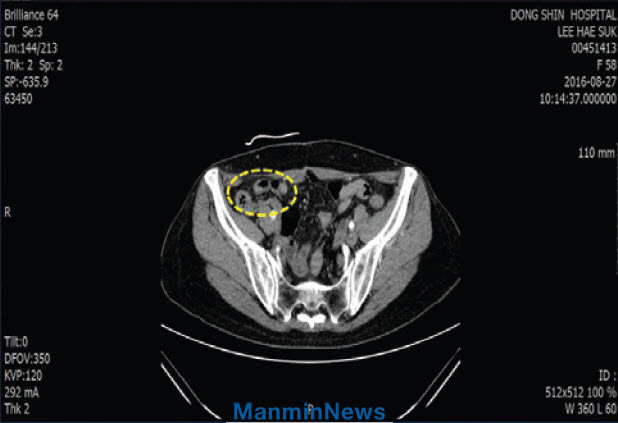

В конце июля 2016 года у меня появилась боль внизу живота, слева. Когда я получила молитву старшего пастора, записанную на телефонном автоответчике, боль уменьшилась. В это время 3-й главный приход готовился к спортивному состязанию по толканию шара, которое должно было состояться во время летнего ретрита «Манмин», и я была выбрана одним из игроков команды. 2 августа, как ни тяжело мне это было, я пришла на тренировку.

3 августа я почувствовала сильную боль внизу живота справа и не могла уснуть. Я обратилась в госпиталь, где мне сделали КТ-сканирование и поставили диагноз – илеит.

Моя подвздошная кишка, рядом с аппендиксом, была сильно воспалена, и вокруг нее образовался гной. Воспаление было настолько серьезным, что задело другие органы. Я услышала, что это может привести к перитониту или сепсису, поэтому нужна срочная операция. Врач назначил операцию на следующий день. Я задумалась над тем, почему я заболела этой болезнью. И осознала, что я обычно всем была недовольна. Я искренне покаялась в этом и после покаяния почувствовала себя счастливой. Я пошла на тренировку, готовясь к предстоящим спортивным состязаниям, а потом вернулась домой. Получив молитву старшего пастора, я пошла спать.

Утром 4 августа у меня началась диарея, и выделения были зелеными. Но у меня не было боли, и я хорошо себя чувствовала. Мой доктор сказал, что у меня больше нет симптомов илеита и операция мне не нужна. Аллилуйя!

КТ-сканирование

До молитвыПодвздошная кишка сильно воспалена, и вокруг нее гной.

После молитвы Воспаление исчезло, и кишечник пришел в норму.